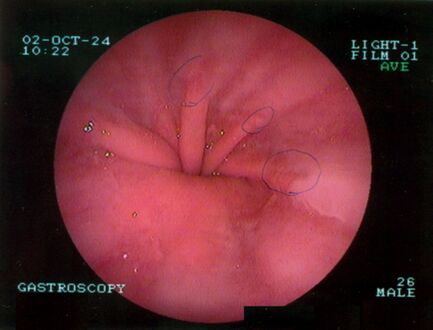

يتم تشخيص فتق الحجاب الحاجز عادةً من خلال سلسلة تصوير الجهاز الهضمي العلوي، التنظير الداخلي، قياس الضغط عالي الدقة، مراقبة درجة حموضة المريء، والتصوير المقطعي المحوسب. يسمح ابتلاع الباريوم كما في سلسلة تصوير الجهاز الهضمي العلوي لرؤية حجم المريء وموقعه وتضيقه. كما يمكنه تقييم حركات المريء. يمكن للتنظير الداخلي تحليل السطح الداخلي للمريء بحثاً عن التآكلات والقرح والأورام.

تنظير الجهاز الهضمي العلوي يصور الفتق الحجابي.

تنظير الجهاز الهضمي العلوي في وضع الانثناء للخلف يظهر الفتق الحجابي من النوع الأول.